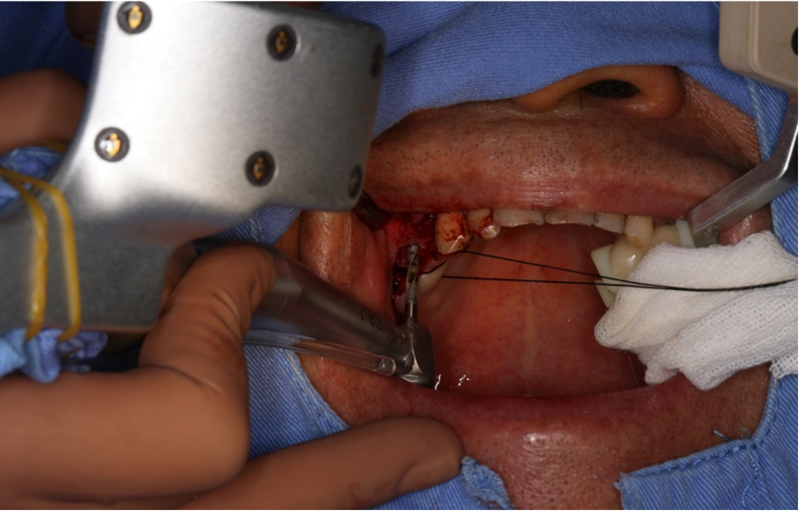

®完成標定及配準

®按照術前方案進行備洞及植體植入

®按照術前方案進行備洞及植體植入,醫(yī)生可以通過屏幕軟件引導對手術中植入點、角度、深度實時追蹤

®對植體深度及方向進行確認